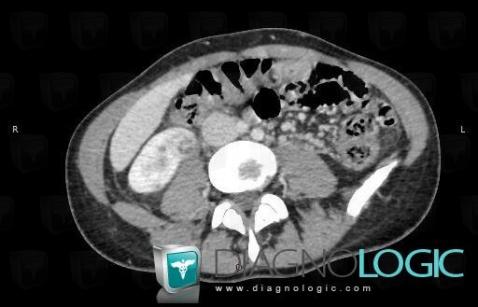

Abscess, Kidney, CT

Here is the specific information in the key image above:

- Diagnosis Abscess, Location(s) Kidney, with gamuts Cystic renal mass